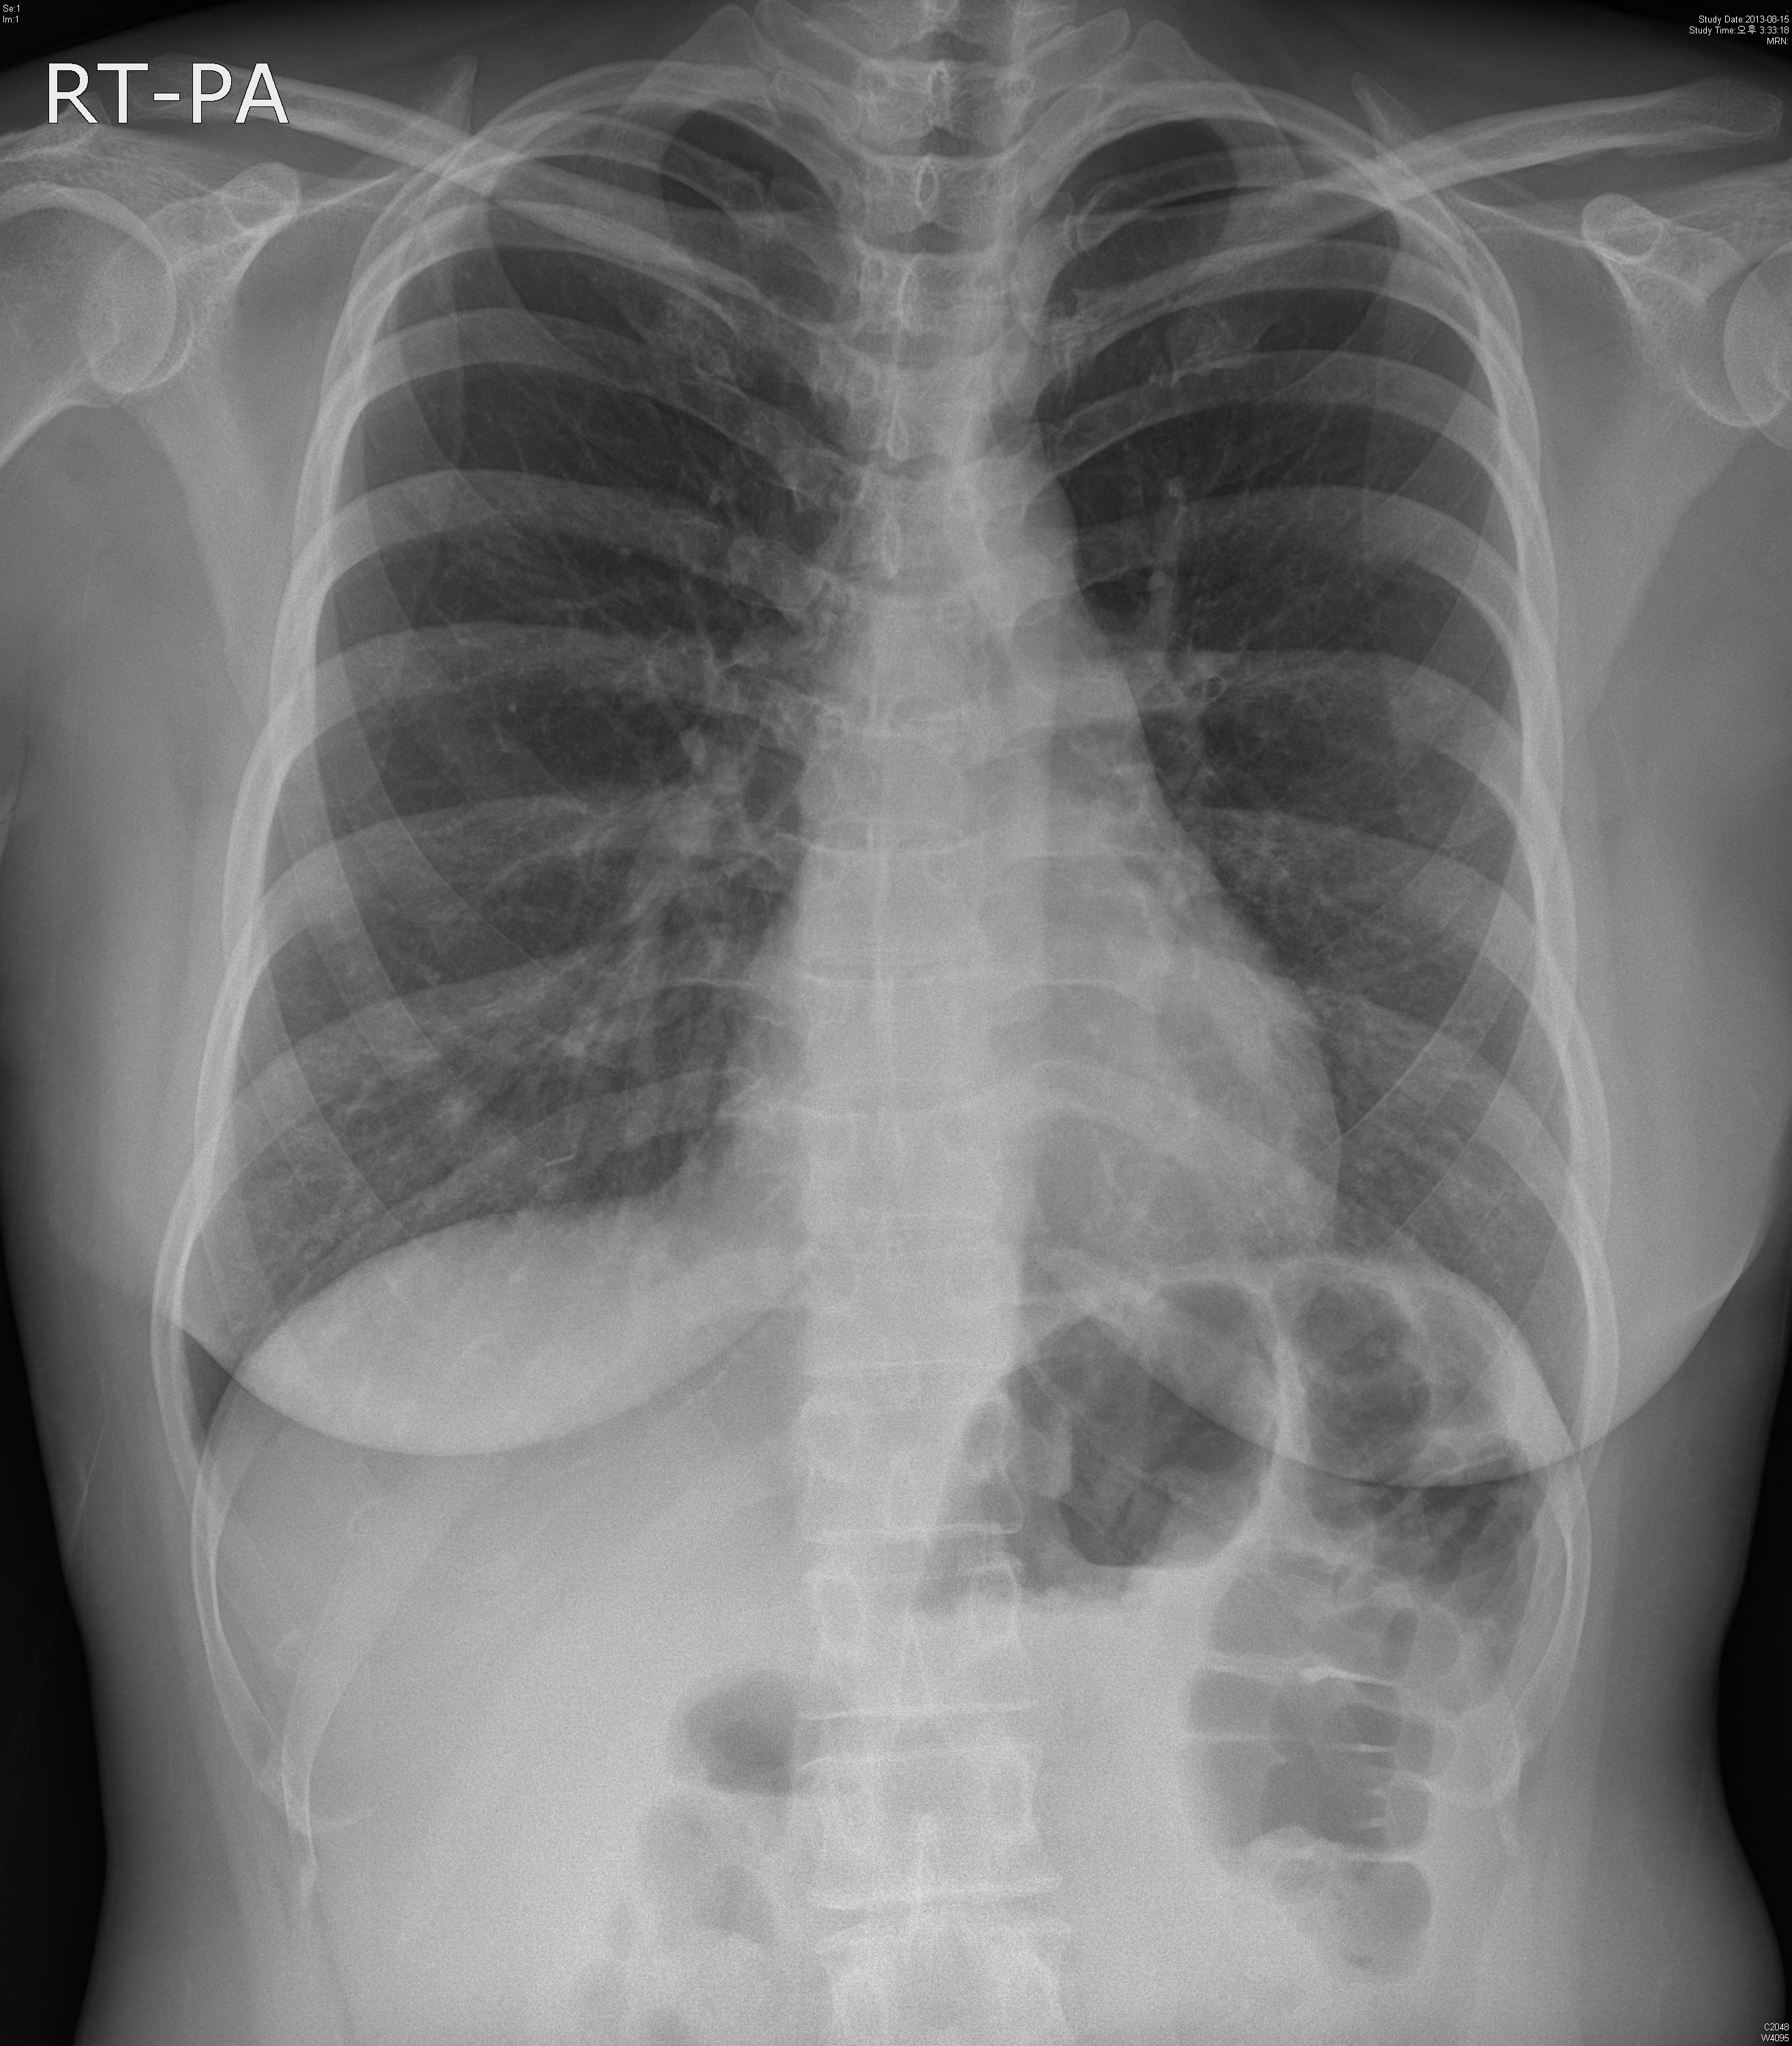

Á¤´ä: Docetaxel induced interstitial pneumonitis

ȯÀÚ´Â breast cancer ¿¡ ´ëÇØ docetaxel based chemotherapy¸¦ ½ÃÇà¹Þ¾Ò°í

ÀÌÈÄ Áõ»ó ¹ß»ýÇÏ¿´½À´Ï´Ù.

Diffuse patchy ground glass opacity in both lungs.

No pleural effusion.

IMP: Most likely interstitial pneumonia such as viral or PCP.

Prednisolone º¹¿ëÇÏ¿© Ä¡·áÇÏ¿´½À´Ï´Ù.

1ÁÖÈÄ DOEµîÀÇ Áõ»óÀº È£ÀüµÇ¾ú°í Steroid tapering Áß¿¡ ÀÖ½À´Ï´Ù.

¾Æ·¡´Â Ä¡·á ÀüÈÄÀÇ »çÁø°ú  Review ÀÔ´Ï´Ù.

Docetaxel induced Interstitial pneumonitis